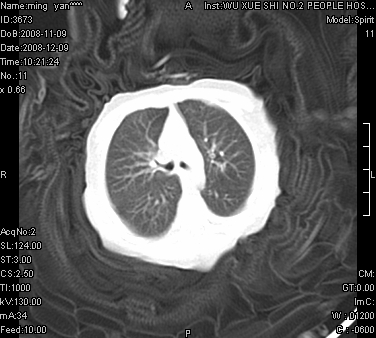

女.30天.咳嗽.喘3天.系三胞胎

考虑右肺下叶先天性肺囊肿,不除外合并右中叶肺发育不全

伴双肺感染

考虑右肺下叶先天性多发性肺囊肿可能。

考虑右肺下叶肺囊肿伴感染,右中叶节段实变或发育不全

这是一个先天性囊性腺瘤样畸形(congenital cystic adenomatid malformation,ccam),属于先天性肺发育异常,最近国外文献重新命名为先天性肺气道畸形(congenital pulmonary airway malformation,cpam),根据发生部位和畸形组织与气管、支气管的关系分成五型。本病以1岁以下婴儿多见,男性多于女性。病因为终末呼吸单元的异常增殖,形成多囊状结构。国内根据影响和病理表现分三型:ⅰ型为单个或多个大囊肿,直径大于2cm;ⅱ型为多个小囊肿,直径小于2cm;ⅲ型为大的非囊肿性病变,但显微镜下观察可见肿块由多发小囊组成(直径小于2mm)。本病可发生于肺内任何一部分,单侧肺占95%,中叶病变相对较少。